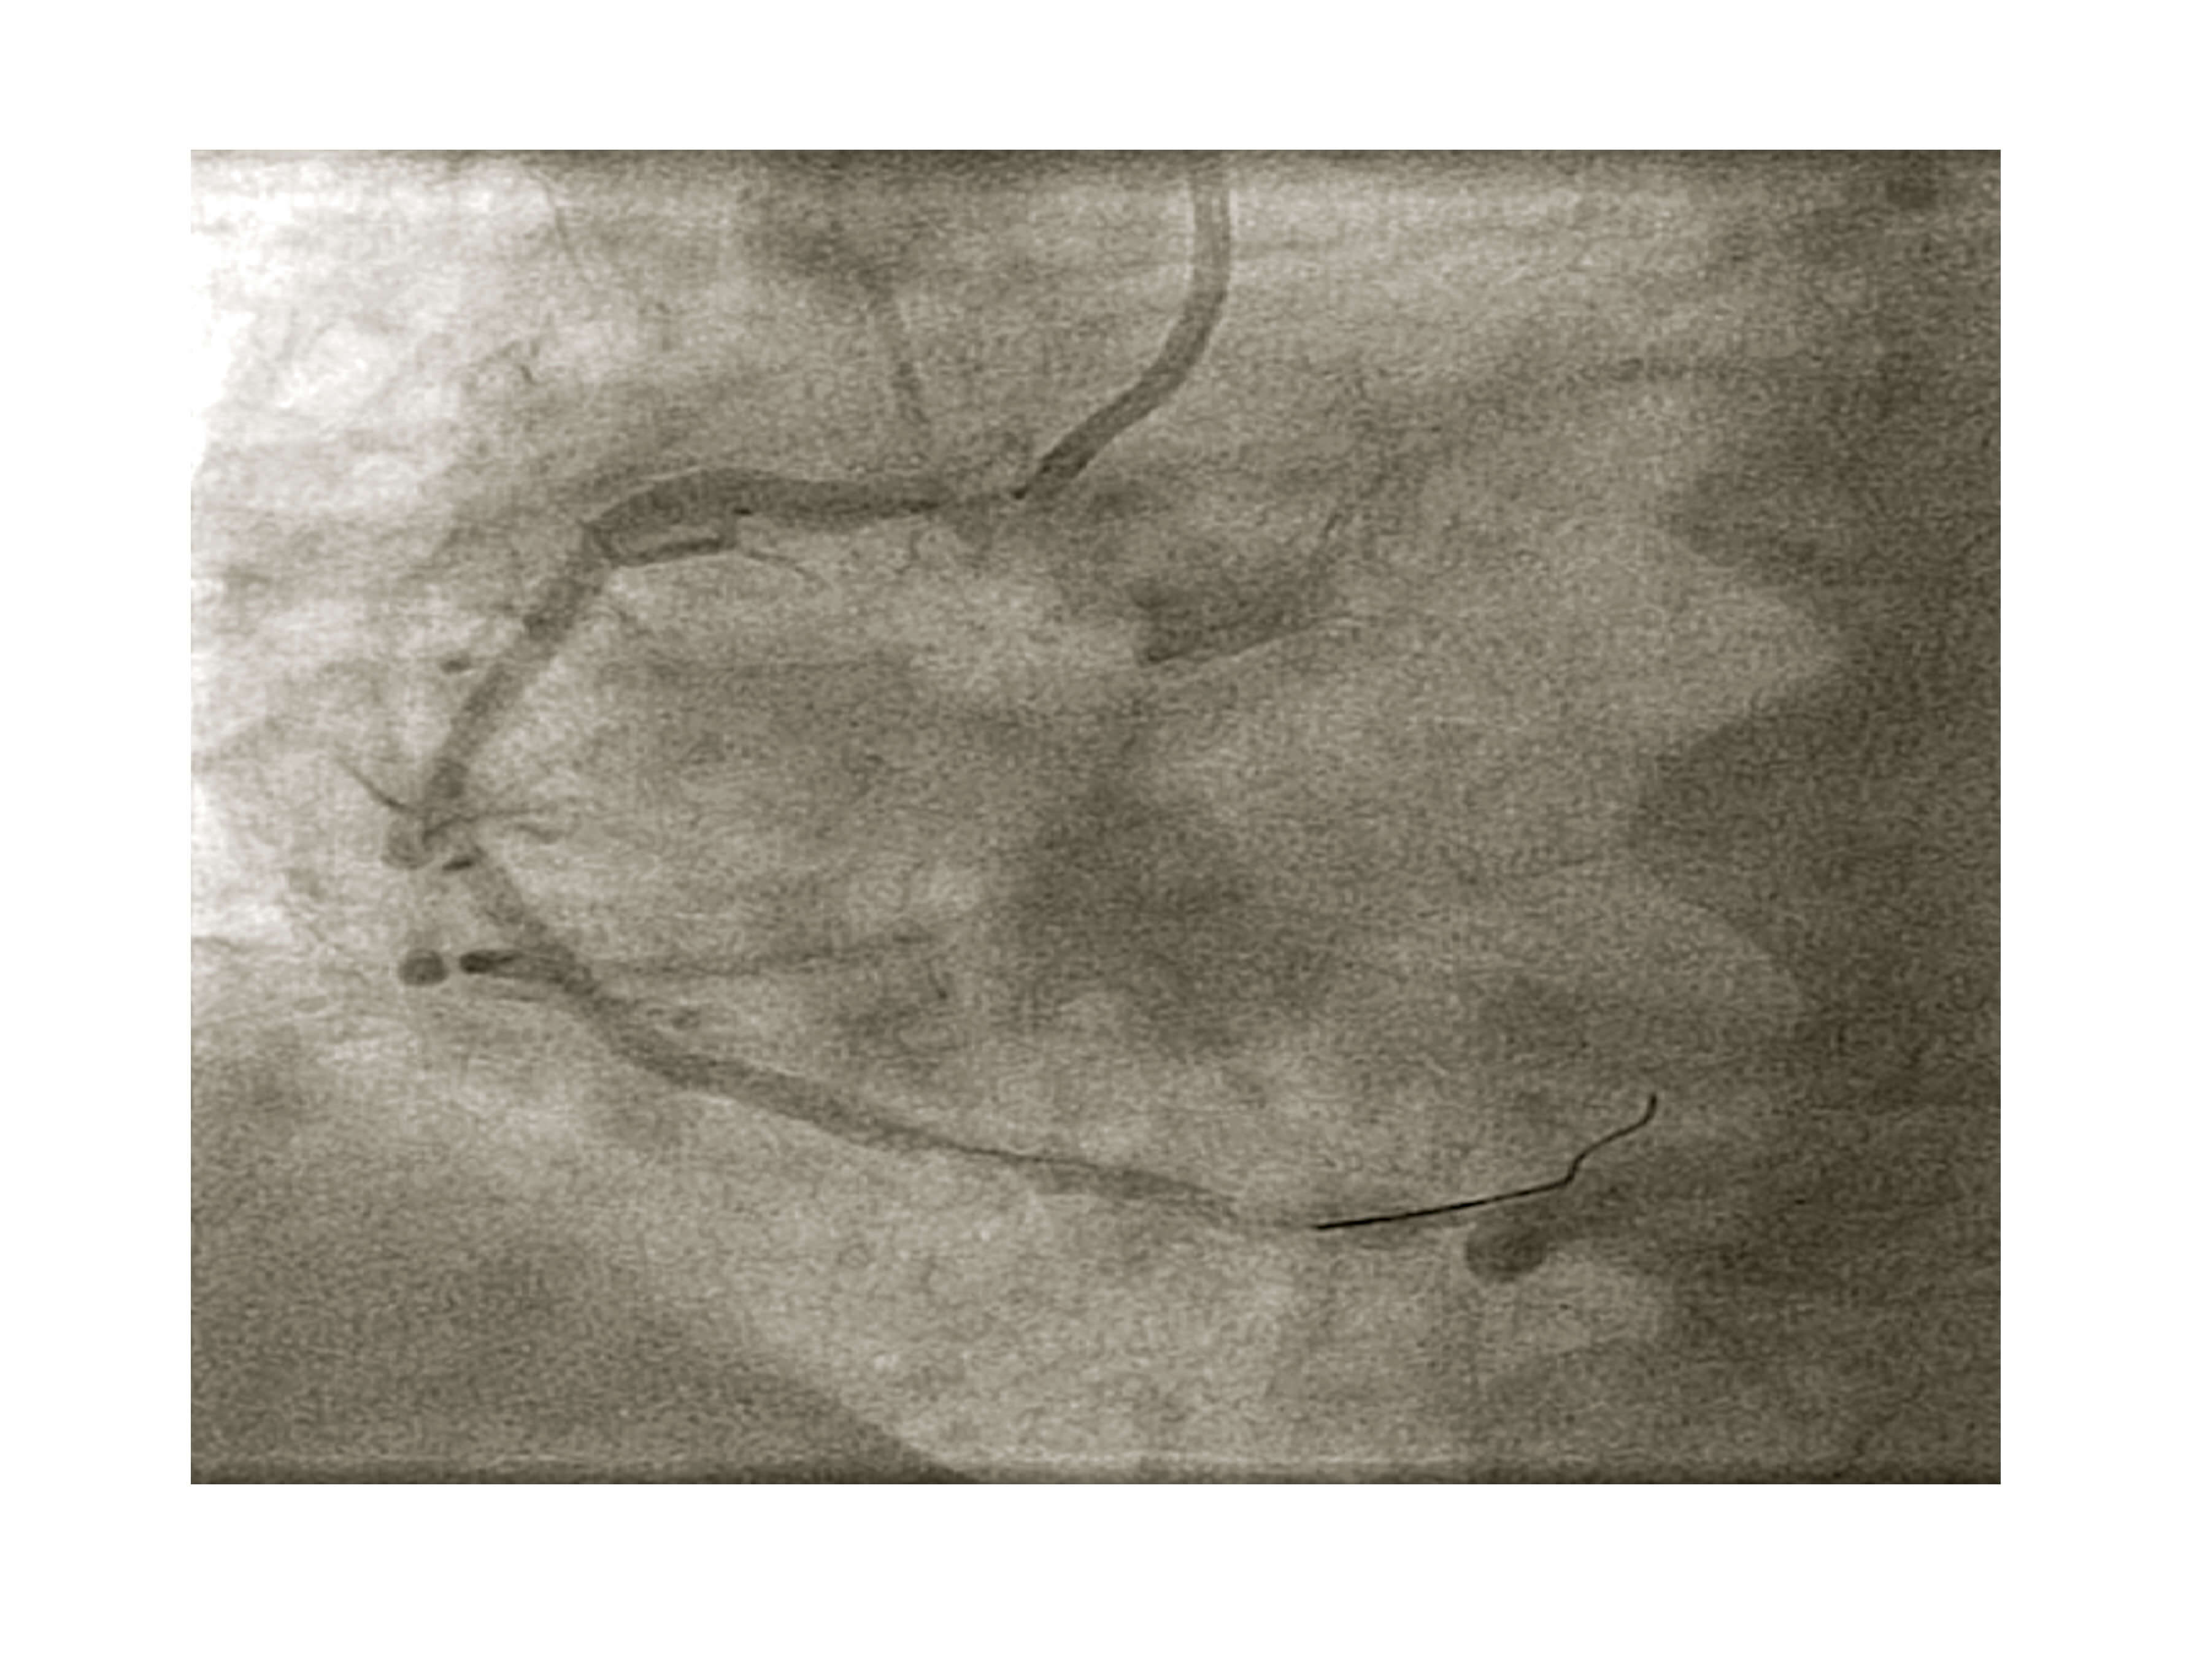

Se procedió a cambio a catéter guía JR de 6 Fr y se pasó una guía de angioplastia Sion (Asahi). Se realizó predilatación con balón no distensible de 3,5 × 10 mm (figura 2) y se eligió un stent liberador de sirolimus Orsiro de 3,5 × 18 mm, cubriendo el ostium (figura 3).

Figura 3. Angiografía previa al implante del stent ajustado al ostium de la arteria coronaria derecha.